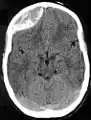

يظهر الورم الدموي فوق الجافية بالتصوير بالأشعة المقطعية والتصوير بالرنين المغناطيسي محدب الشكل؛ لأنه يتوقف عند درز الجمجمة، حيث تلتصق الأم الجافية بإحكام على الجمجمة، وبالتالي فإنه يتوسع نحو الداخل ناحية الدماغ بدلا من نحو الجمجمة، كما يحدث في الورم الدموي تحت الجافية. ويسبب الشكل الذي يشبه العدسة للورم الدموي ظهور ذلك النزيف ليكون "عدسي الشكل".

أشعة مقطعية غير متباينة لورم دموي ناجم عن رضة حادة في المنطقة الأمامية الصدغية اليسرى